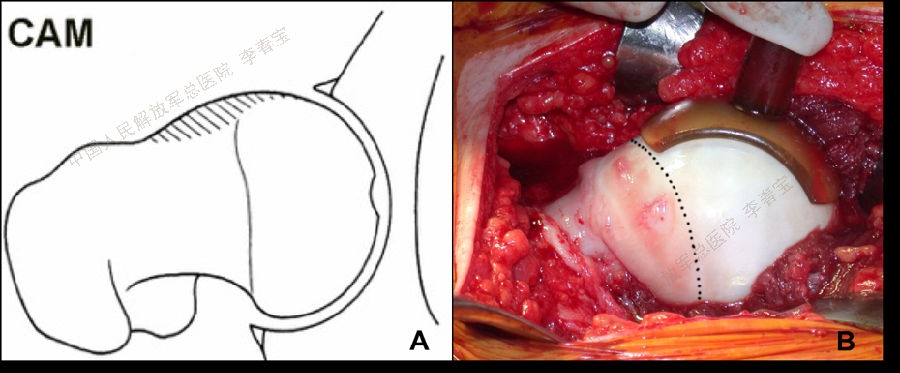

2. 髋关节撞击症

髋关节撞击征(femoroacetabular impingement, FAI)是引起中青年,特别是运动量较大者髋关节疼痛的主要原因,也是引起早期骨关节炎的重要因素。按受累解剖部位形态学改变,FAI 可分为:(1)凸轮型撞击(cam impingement);(2)钳夹型撞击(pincer impingement);(3)凸轮钳夹混合型撞击(mixed type)。该病好发于喜欢运动的青壮年,患者常有不明原因的髋关节慢性疼痛,以腹股沟区最为多见,也可出现股骨后侧和外侧疼痛,同时伴有髋关节活动受限,以屈曲内旋受限最为显著。通过髋部X片(包括骨盆正位X线片、髋关节穿桌侧位、蛙式侧位X线片、屈髋侧位片或假斜位片)、MRI和CT检查一般不难诊断。一般经休息、限制髋关节运动、服用非甾体抗炎药以及封闭治疗等保守治疗无效可考虑手术治疗。治疗方面,早期主要是通过股骨头脱位技术进行开放手术治疗,目前的主流是通过髋关节镜微创技术进行治疗,包括镜下清理凸轮畸形,恢复股骨头颈区的自然弧度;清除髋臼边缘的骨赘和适当磨除髋臼周围影响髋关节活动的骨质,以减少髋臼前方的过度覆盖,最后把髋臼盂唇剩余部分缝合固定在骨面或髋臼缘上。